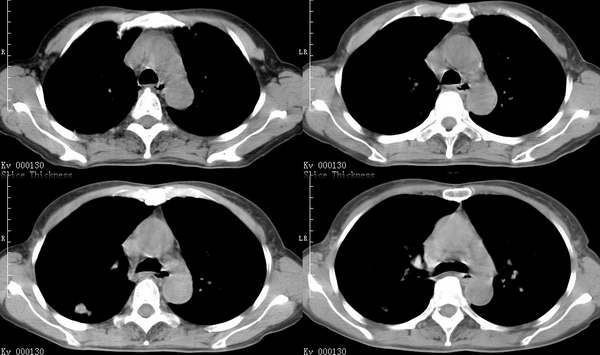

咳嗽6月低热1月!

右上叶背段及左下叶见斑片状密度不均模糊影,右中叶支气管狭窄,中叶密度增高,体积缩小.纵隔未见明确淋巴结.结论:1、两俩结核,右中叶支气管内膜结核,并中叶肺不张。2、两肺炎;右中心型肺癌,并阻塞性肺不张。

右肺上叶尖后段及左肺舌叶 下叶见斑片状密度不均模糊影,右中叶支气管狭窄,中叶密度增高,体积缩小.纵隔未见明确淋巴结。考虑:双肺结核伴右侧中叶不张。

纵隔淋巴结增大,中叶肺不张.肺癌可能性大

右上叶背段及左下叶见斑片状密度不均模糊影,右中叶支气管狭窄,近端未见肿块,中叶密度增高,体积缩小.纵隔未见明确淋巴结.结论:两肺结核,右中叶支气管内膜结核,并中叶肺不张。肺纹理粗乱,有慢支表现,伴有感染存在。

ct显示病灶呈多灶性分布,主要分布在双肺上叶后段,右肺中叶及左肺下叶,右肺上病灶内可见点状钙化,纵隔内示淋巴结钙化,结合病史6个月伴低热,考虑感染性病变,结核可能大.